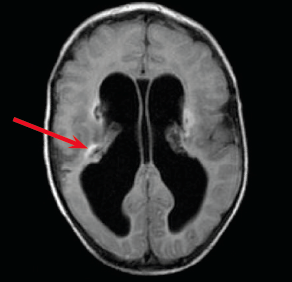

Anand Gourishankar, MD; Robert Lapus, MD

A 2-month-old boy had been doing well after birth until about 7 or 8 weeks of life. His parents felt that he was not smiling, and was only looking to the right.